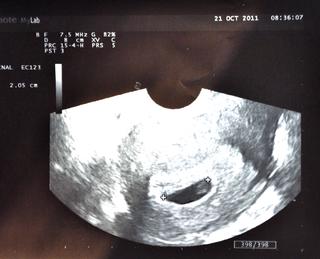

Ahojte, rada by som sa k Vám pridala. 🙂 zajtra začínam 10tt, TP 10.06. Je to naše druhé dieťatko, doma už máme dvojročného Tobiáška. Býva mi zle vlastne celodenne, to som v prvom tehotenstve nemala. 😝 Bruško už pekne vykukuje, hlavne večer. Na kontrole som bola naposledy 6+5tt, ďalšia + odbery na NT screening ma čaká 14.11., neviem sa dočkať 😉 Pridávam fotku z poslednej kontroly, kde už krásne blikalo srdiečko a aj našeho oslávenca 😉 Krásny víkend všetkým